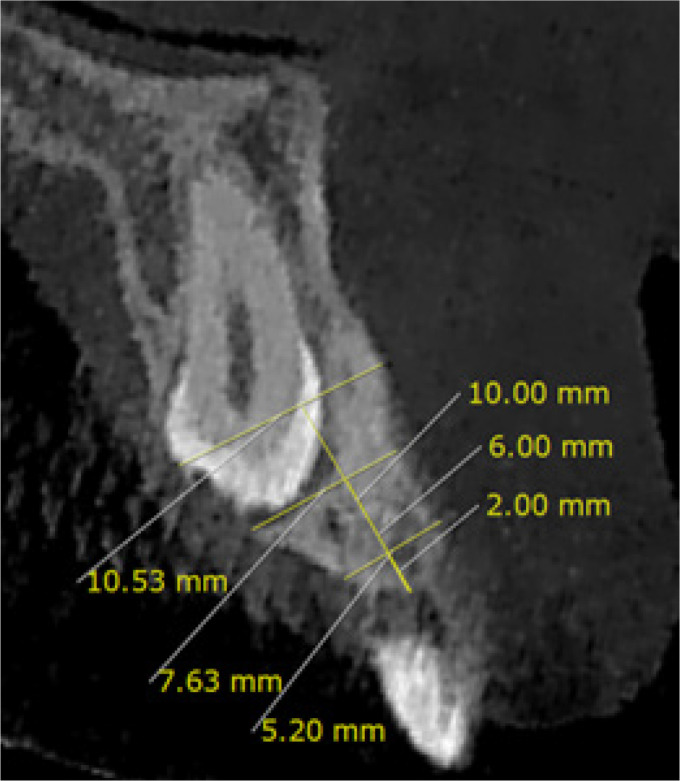

Material and methods: In this cross-sectional descriptive-analytical study, 47 CBCT images of unilateral buccally impacted maxillary canines and 47 CBCT images of unilateral palatally impacted maxillary canines were examined. Several morphological variables were compared between the impacted and non-impacted sides, and between the buccal and palatal impaction types.

Results: Gender and age were not significantly associated with the canine impaction type. The alveolar bone height at the impacted side was significantly greater in the buccally impacted group than in the palatally impacted group (p = 0.016). In a comparison of the impacted and non-impacted sides, all variables of alveolar bone thickness at depth of 2 mm, maxillary arch width, and palatal volume had significantly smaller values in the impacted side in both buccally and palatally impacted groups (p < 0.05). The alveolar bone was significantly thicker at the depth of 10 mm in the impacted side of the buccal group (p = 0.024). The maxillary arch perimeter was significantly smaller in the impacted side of the buccal group (p = 0.008). The palatal depth did not significantly differ between the groups.